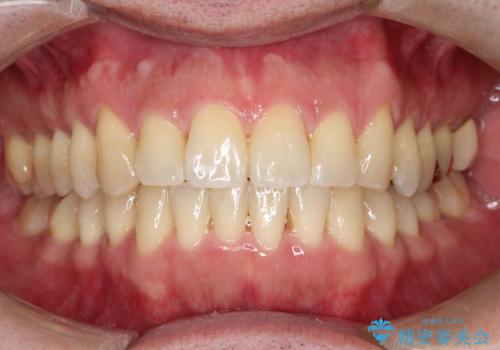

ワイヤーによる全体的ながたつきの矯正治療